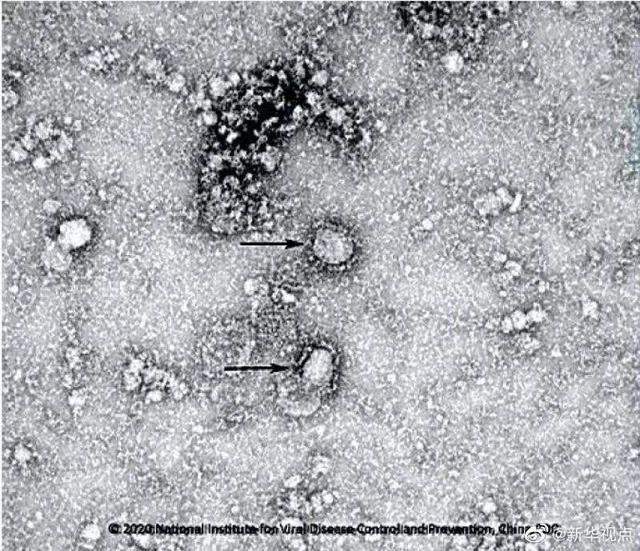

报道称 , 为了区别这种病毒 , 科学家一直将其称为“新型冠状病毒” 。 冠状病毒因在显微镜下看有冠状突起而得名 。